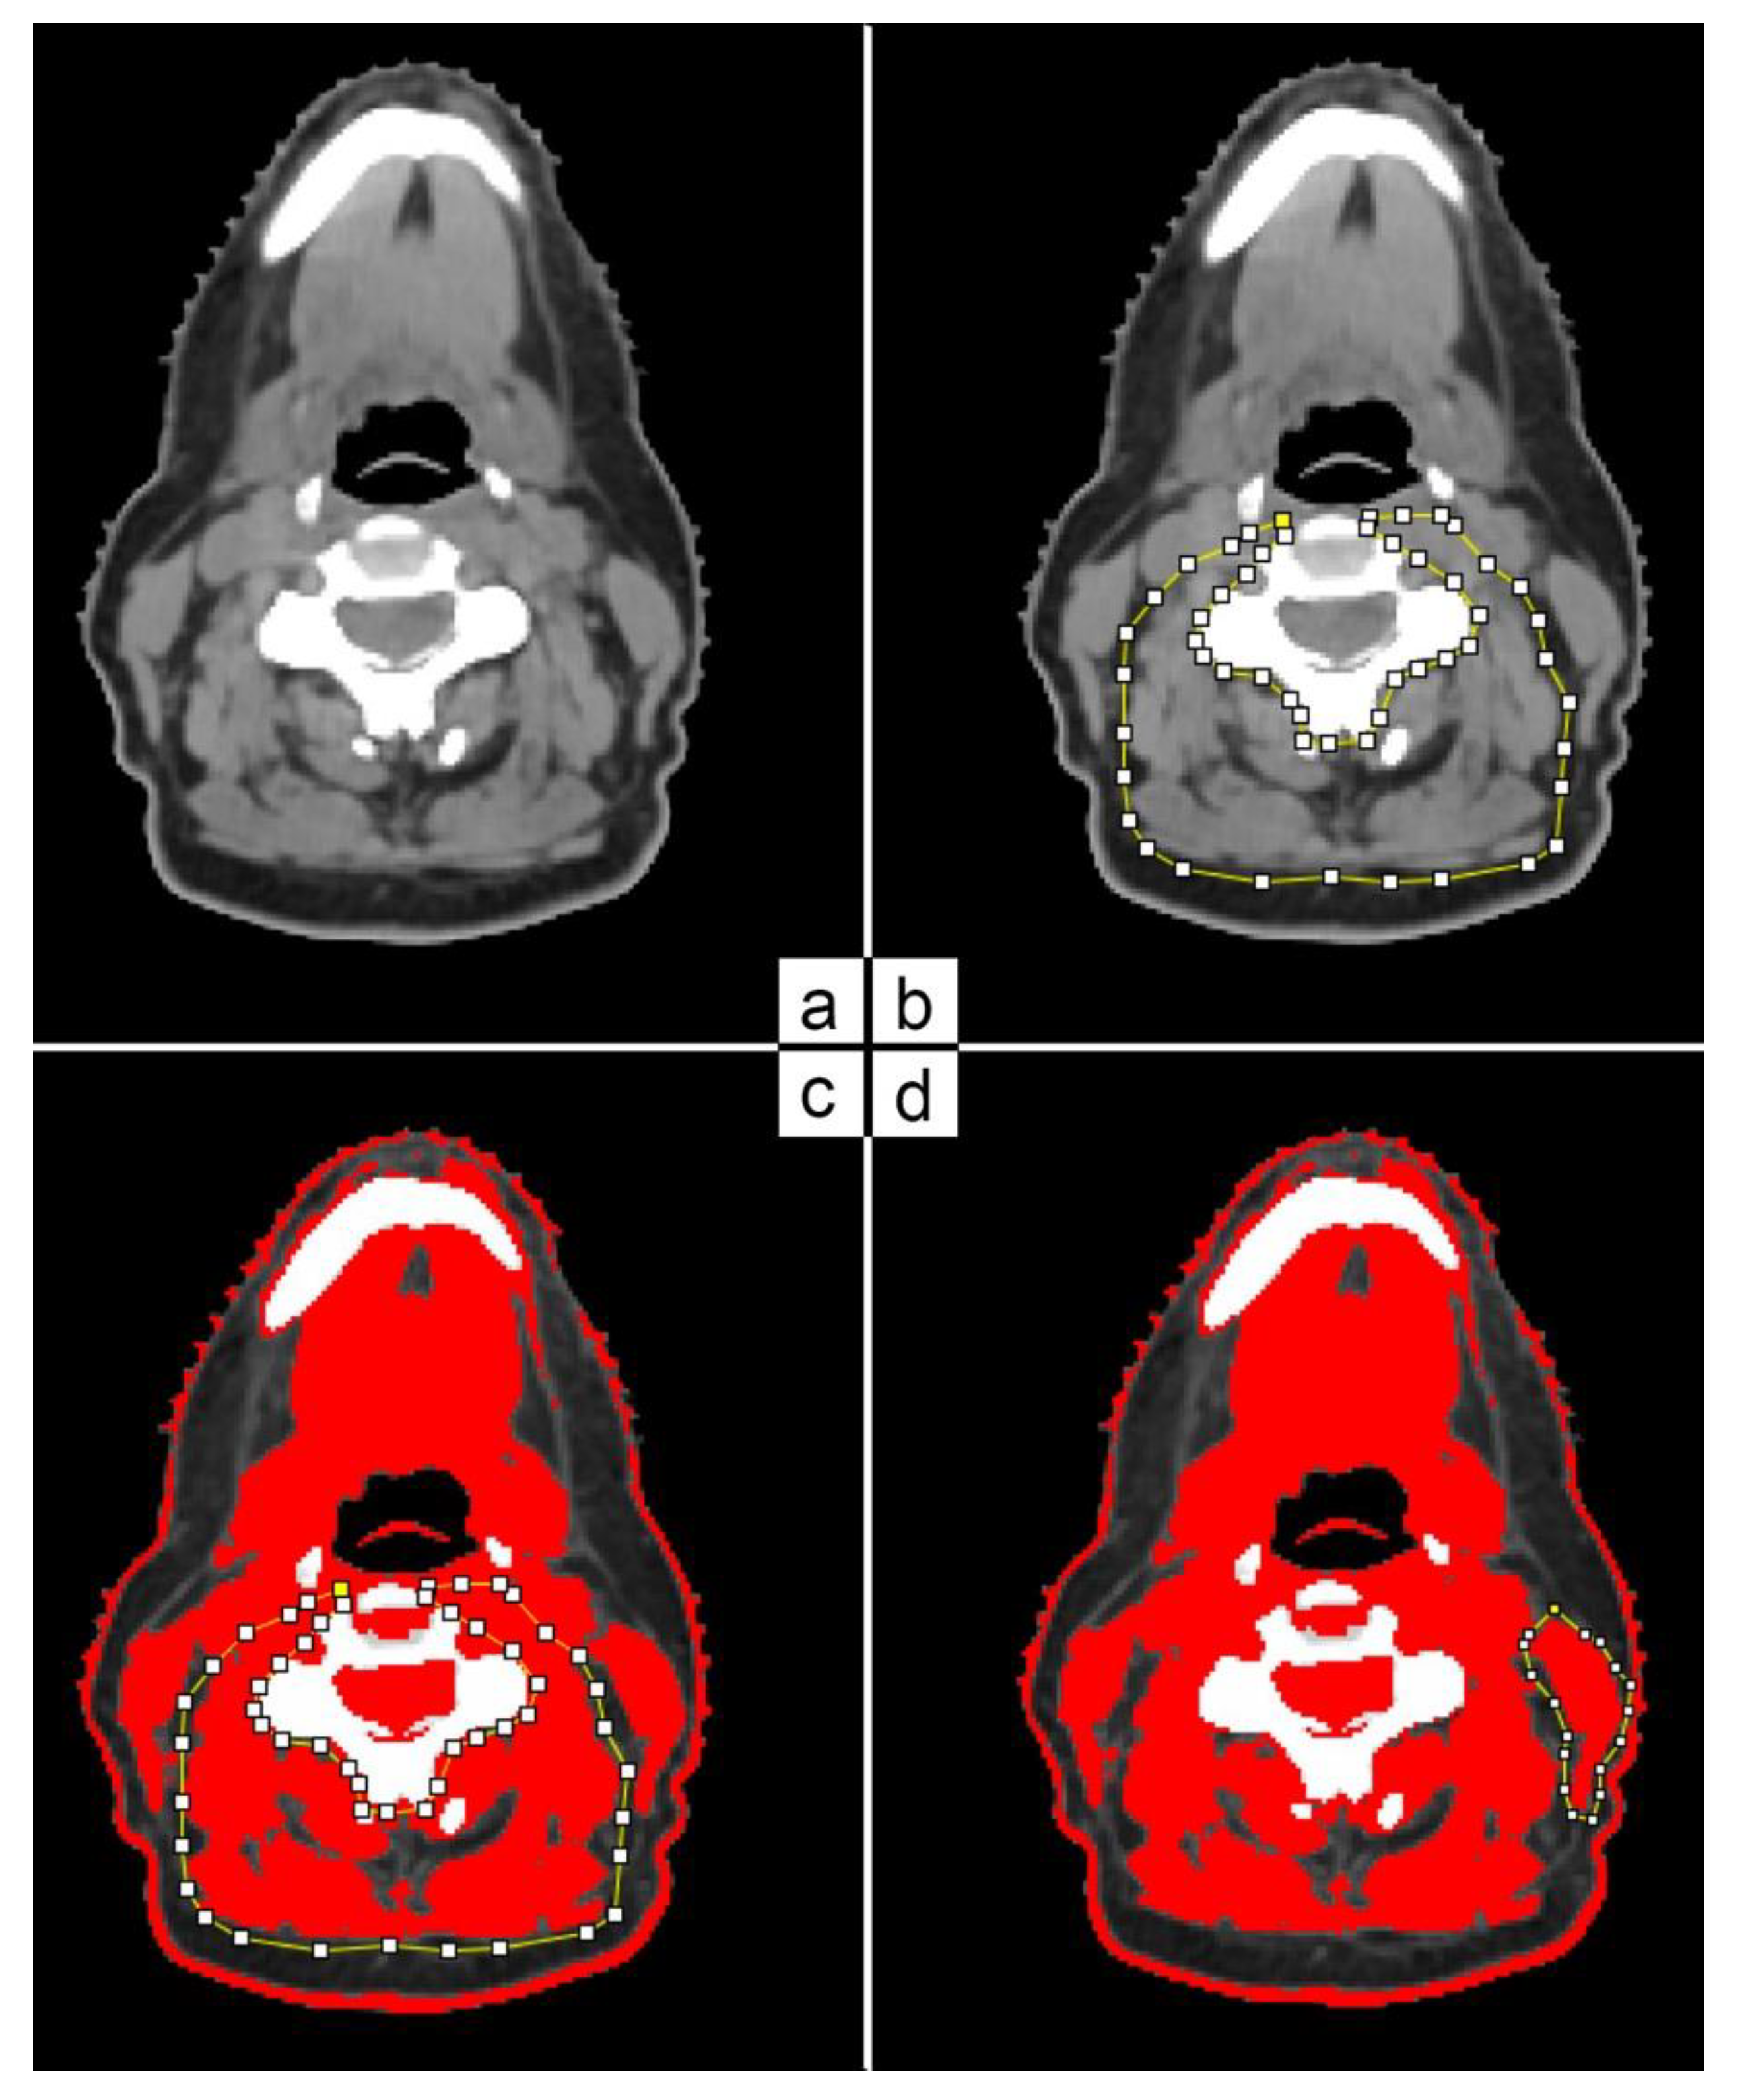

Cross-section area (CSA) was measured using a single slice at the level of C3 vertebra on patients’ t0 and t3 CT scans. The selected slice had to show the vertebral transverse process and the entire vertebral arc (Figure 1a). A resident radiation oncologist and an experienced radiation oncologist performed the muscle area delineation and analysis using ImageJ software (Figure 1b). Skeletal muscle area was defined as the pixel area between the radiodensity range of −29 and +150 Hounsfield units (HUs), encompassing muscles from very low and low density (−29 to +34 HU) to normal density (+35 to +150 HU) [17,18]. In the case of C3 paravertebral muscle areas (Figure 1c), the contralateral sternocleidomastoid (SCM) muscles were delineated (Figure 1d).

Figure 1.

C3 paravertebral and SCM area delineation on CT scan based on HU threshold.

The CSA (cm2) of the skeletal muscle was then calculated as the sum of the areas of paravertebral muscles plus twice the value of a single SCM muscle.